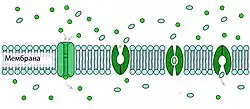

Межклеточный транспорт

В капиллярах периферических органов и тканей транспорт веществ осуществляется в основном через фенестра́ции сосудистой стенки и межклеточные промежутки. В норме между клетками эндотелия сосудов мозга такие промежутки отсутствуют. В связи с этим питательные вещества проникает в мозг лишь через клеточную мембрану[118]. Вода, глицерин и мочевина являются примерами тех небольших поляризованных молекул, которые могут свободно диффундировать через плотные контакты между эндотелиальными клетками ГЭБ[119].

Свободная диффузия

Самой простой формой транспорта через ГЭБ является свободная (или пассивная) диффузия. Она может осуществляться как через клеточные мембраны эндотелиоцитов, так и через плотные межклеточные контакты. Для диффузии веществ движущей силой является разница концентраций. Диффузия веществ пропорциональна градиенту концентраций в кровеносном русле и ткани мозга. Для неё не требуется затрат клеточной энергии[120].

Липофи́льные структурные элементы клеточной мембраны, а также плотные межклеточные контакты снижают количество веществ, которые могут свободно диффундировать через ГЭБ. Проницаемость ГЭБ напрямую зависит от липофильности каждого конкретного вещества[121].

Проницаемость ГЭБ также зависит от молярной массы вещества. Молекулы с массой более 500 г/моль не могут диффундировать через ГЭБ. В то же время ГЭБ не является механическим барьером, который свободно пропускает молекулы меньшего размера и не пропускает большего. Процесс клеточной диффузии является динамическим, при этом он легче для веществ с молярной массой 200 г/моль, чем для веществ с 450 г/моль[41][122]. Чем липофильнее и меньше вещество, тем легче оно диффундирует через клеточную мембрану[6].

Канальцевая проницаемость

Небольшие полярные вещества, например молекулы воды, с трудом могут диффундировать через гидрофобные отделы клеточной мембраны эндотелиоцита. Несмотря на это доказана высокая проницаемость ГЭБ для воды[134].

В клеточной мембране эндотелиоцита располагаются специальные гидрофильные каналы — аквапоры. В эндотелии периферических сосудов они образованы белком аквапорином-1 (AQP1), экспрессия которого ингибируется астроцитами в клетках сосудов мозга[135]. На поверхности мембран клеток капиллярной сети мозга представлены в основном аквапорин-4 (AQP4) и аквапорин-9 (AQP9)[136].

Через аквапоры происходит регуляция содержания воды в веществе мозга. Они делают возможным быструю диффузию воды как в направлении мозга так и в направлении сосудистого русла в зависимости от осмотического градиента концентраций электролитов[137]. Для глицерина, мочевины и ряда других веществ на поверхности клеточных мембран формируются собственные каналы — акваглицеропорины. В ГЭБ они представлены в основном белком аквапорином-9 (который также образует аквапоры)[138].

Процесс транспорта молекул через специализированные каналы осуществляется быстрее активного переноса с помощью специальных белков транспортёров. В то же время различные биологически активные вещества могут активировать или инактивировать транспортные каналы расположенные на клеточных мембранах[118].

Облегчённая диффузия

Особой формой диффузии через клеточную мембрану является облегчённая диффузия. Целый ряд необходимых для мозга веществ, как например, глюкоза и многие аминокислоты, полярны и слишком велики для непосредственной диффузии через клеточную мембрану. Для них на поверхности клеточных мембран эндотелиоцитов располагаются специальные транспортные системы. Например, для глюкозы и аскорбиновой кислоты (витамина С)[139] это GLUT-1-транспортёр. Их количество на поверхности обращённой в полость сосуда в 4 раза больше, чем на обращённой к мозгу.

Кроме транспортёров глюкозы на поверхности эндотелия располагаются множество белковых молекул выполняющих подобную функцию для других веществ. Так например MCT-1 и MCT-2 ответственны за перенос лактата, пирувата, мевалоновой кислоты, бутиратов и ацетатов. SLC7 транспортирует аргинин, лизин и орнитин. В геноме мыши выявлено 307 генов отвечающих за синтез SLC-белков, ответственных за облегчённую диффузию через клеточную мембрану различных веществ[140].

Транспортёры могут осуществлять перенос веществ в одном либо двух направлениях[141]. В отличие от активного транспорта облегчённая диффузия направлена в сторону пространства (внутри- или внеклеточного) с меньшей концентрацией вещества и не требует затрат клеточной энергии.

Активный транспорт

В отличие от пассивного транспорта, не требующего затрат энергии, активный заключается в переносе веществ в пространство с большей концентрацией вещества и требует больших затрат клеточной энергии, получаемой при распаде молекул АТФ[118]. При активном транспорте веществ из кровеносного русла в ткань мозга говорят о притоке вещества (англ. influx), в обратном направлении — об оттоке (англ. efflux).

В ГЭБ располагаются активные транспортёры энкефалина[142][143], антидиуретического гормона[144], [D-пеницилламин2,D-пеницилламин5]-энкефалина (DPDPE)[145].

Первым идентифицированным Efflux-транспортёром ГЭБ[146] является Р-гликопротеин, который закодирован геном MDR1.[147][148]

Впоследствии были открыты относящийся к классу ABC-транспортёров Multidrug Resistance-Related Proteine (MRP1)[149], Breast Cancer Resistance Proteine (BCRP)[150][151] расположенный преимущественно на обращённой в просвет сосуда поверхности[152][153].

Некоторые Efflux- и Influx-транспортёры являются стереоселективными, то есть переносят лишь определённый стереоизомер (энантиомер) того или иного вещества. Так например, D-изомер аспарагиновой кислоты является прекурсором N-метил-D-аспартата (NMDA), который влияет на секрецию различных гормонов: лютеинизирующего гормона, тестостерона или окситоцина[154]. L-изомеры аспарагиновой и глутаминовой кислоты являются стимулирующими аминокислотами и их избыток токсичен для ткани мозга[155]. Efflux-транспортёр ASCT2 (аланин-серин-цистеин-транспортёр) ГЭБ выводит в кровеносное русло L-изомер аспарагиновой кислоты, чьё накопление имеет токсический эффект. Необходимый для формирования NMDA D-изомер поступает в мозг с помощью других транспортных белков (EAAT, SLC1A3, SLC1A2, SLC1A6)[25][156][157].

В эпилептогенной ткани в эндотелии и астроцитах представлено большее количество белка Р-гликопротеина по сравнению с нормальной тканью мозга[158][159].

На клеточных мембранах эндотелиоцитов располагаются также транспортёры анионов (OAT и OATP)[160][161]. Большое количество Efflux-транспортёров выводят из эндотелиоцитов целый ряд веществ в кровеносное русло[120].

Для многих молекул до сих пор не ясно выводятся ли они путём активного транспорта (с затратами клеточной энергии) или путём облегчённой диффузии[25].

Везикулярный транспорт

Рецептор-опосредованный трансцитоз

С помощью рецептор-опосредованного трансцито́за происходит перенос больших молекул. На обращённой в просвет сосуда поверхности клетки расположены специальные рецепторы для опознавания и связывания определённых веществ[23]. После контакта рецептора с веществом-мишенью происходит их связывание, участок мембраны инвагинируется в полость клетки и образуется внутриклеточный пузырёк — везикула. Затем она перемещается к обращённой к нервной ткани поверхности эндотелиальной клетки, сливается с ней и высвобождает связанные вещества. Таким образом во внеклеточное пространство мозга переносятся состоящий из 679 аминокислот белок трансферрин массой 75,2 кДа[162], липопротеины низкой плотности из которых образуется холестерин[130][163], инсулин[164] и другие пептидные гормоны[23].

Абсорбцио-опосредованный трансцитоз

Одним из подвидов везикулярного транспорта является абсорбцио-опосредованный трансцитоз. Отмечается «прилипание» ряда положительно заряженных веществ (катионов) к отрицательно заряженной клеточной мембране с последующем образованием везикулярного пузырька и его переносом к противоположной поверхности клетки. Данный вид транспорта также называется катионным. Он проходит относительно быстрее рецептор-опосредованного трансцитоза[165][166][167][168].